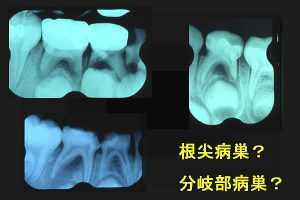

さて乳歯の歯周組織炎のデンタルX線フイルムを見ると、多くのケースに根分岐部に病巣が認められる。

(図1)

永久歯では,根分岐部に及ぶ病巣は少ない。

しかし、乳歯ではどうして多いのだろう?

これは、歯髄腔から根分岐部への側枝が多いことが予想される。

交換のため吸収される運命にある乳歯なら当然だ。

論文を検索すると、下顎第1乳臼歯において、側枝の割合は60%との記述があった。

こう考えれば乳臼歯の髄床底は、“目に見えない第4の根管”と言える。